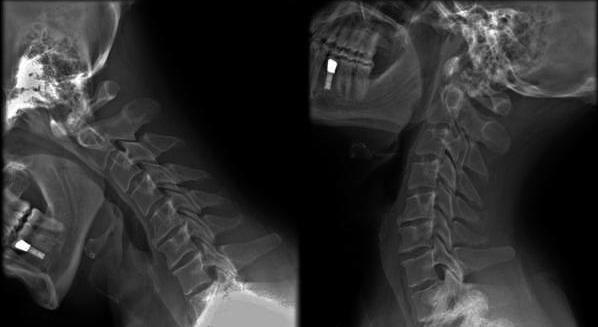

Процесс диагностики начинается с общего осмотра и опроса больного, а также со сбора анамнеза. Для дифференциальной диагностики, пациент сдает анализы на состояние крови и мочи. Для подтверждения первоначального диагноза, используется рентгенографическое обследование в нескольких проекциях. Оценка связочного аппарата и состояния межпозвоночных дисков дается при проведении магнитно-резонансной томографии (МРТ) и компьютерной томографии (КТ).

Лечение нарушений статики шейного отдела позвоночника должно планироваться лечащим врачом после проведения диагностических мероприятий. Заниматься самолечением в этом случае запрещено. В первую очередь врач проводит исследование. Рентгенография и МР помогает точно диагностировать заболевание и понять, в каком состоянии находятся связки, позвонки и диски. На основании результатов диагностики, а также информации, полученной после полного осмотра пациента, врач точно выбирает метод лечения. Чаще всего терапия напрямую зависит от места распространения поражения.

Далее назначаются лабораторные методы (общий анализ крови и мочи) и аппаратные методики исследования (рентгенография, КТ, МРТ).

Справка. Наиболее информативным методом в этом случаев является МРТ, поскольку оно позволяет оценить состояние всех структур, тканей.

Диагностика